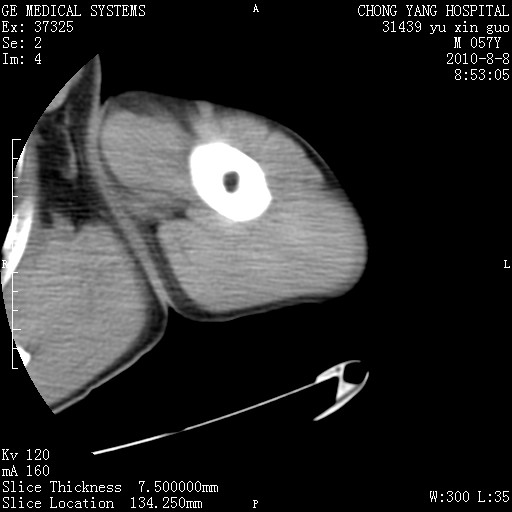

标题: CT28267:M57Y 上臂包块8年余。 [打印本页]

标题: CT28267:M57Y 上臂包块8年余。

典型脂肪瘤改变

包膜光滑、完整的脂肪密度肿块,支持脂肪瘤。

脂肪瘤。有ct值?